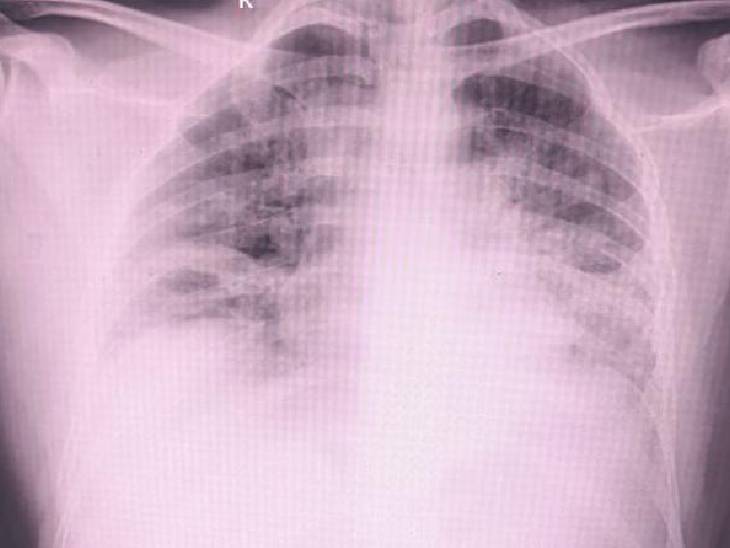

इस स्थिति को मेडिकल भाषा में डिफ्यूज एल्वियोलर प्रोटीनोसिस कहा जाता है। इसमें फेफड़ों की हवा वाली थैलियों में प्रोटीन भर जाता है, जिससे ऑक्सीजन का आदान-प्रदान रुकने लगता है। यही कारण था कि मरीज को सांस लेने में अत्यधिक परेशानी हो रही थी और उसका ऑक्सीजन स्तर लगातार गिरता जा रहा था।

क्या है सिलिकोसिस और क्यों है यह जानलेवा सिलिकोसिस सिलिका नामक बेहद बारीक धूल के कणों से होने वाली बीमारी है। ये कण सांस के साथ फेफड़ों में पहुंच जाते हैं और वहां जमा होकर फेफड़ों की कोमल झिल्लियों को नुकसान पहुंचाते हैं। धीरे-धीरे फेफड़े स्पंज जैसे नरम रहने के बजाय पत्थर की तरह सख्त हो जाते हैं।

जैसे-जैसे बीमारी बढ़ती है, मरीज को सांस लेने में तकलीफ, लगातार खांसी, थकान और ऑक्सीजन की कमी महसूस होने लगती है। अंतिम चरण में शरीर को पर्याप्त ऑक्सीजन नहीं मिल पाती और मरीज की मौत तक हो सकती है।